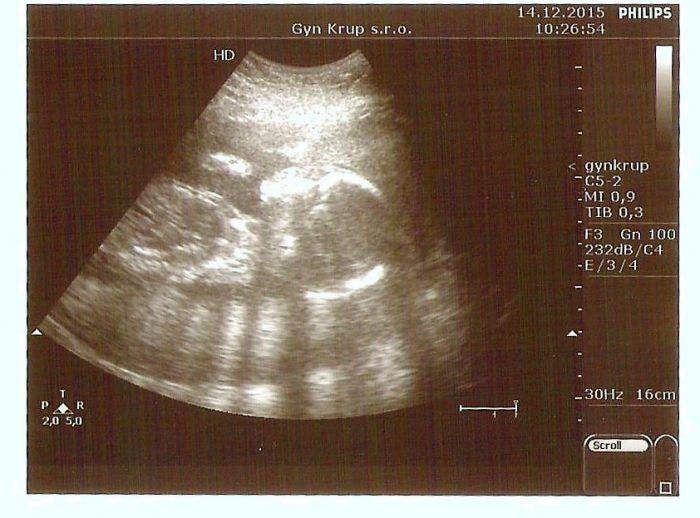

Ahoj holky,tak dnes mám uz po velkem ultrazvuku. Vše v pořádku,dr.mi ukázal hlavičku,srdíčko,nohy ruce..no prostě celé mimčo. Vše je prý naprosto v pořádku. Takže super.Další kontrola až 4.1. takže za 3 týdny přikládám foto našeho 420 gramového mimuška...

To je krasna fotecka ! Gratuluji:)